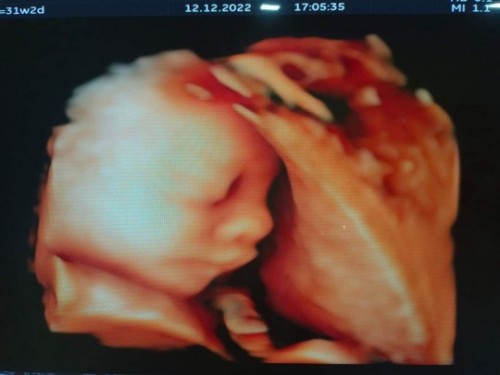

กำหนด11กุมภา 31w2d น้ำหนัก1,624 ค่ะ🥰